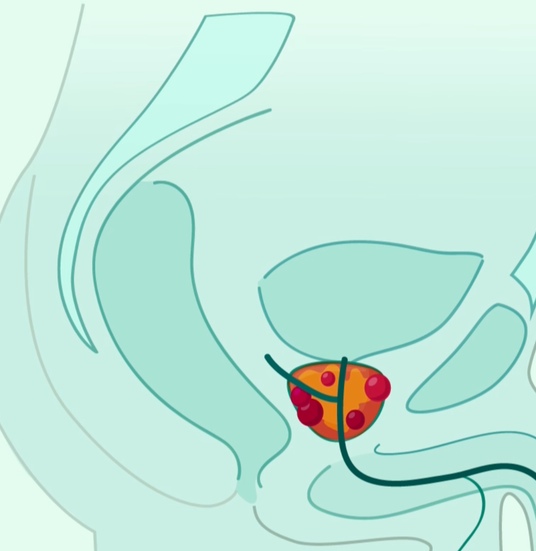

8. Αυξάνεται ο κίνδυνος εμφάνισης καρκίνου

Για τους άντρες, αυξάνεται ο κίνδυνος εμφάνισης καρκίνου του προστάτη, όταν δεν κάνουν

$eξ για μεγάλες χρονικές περιόδους.